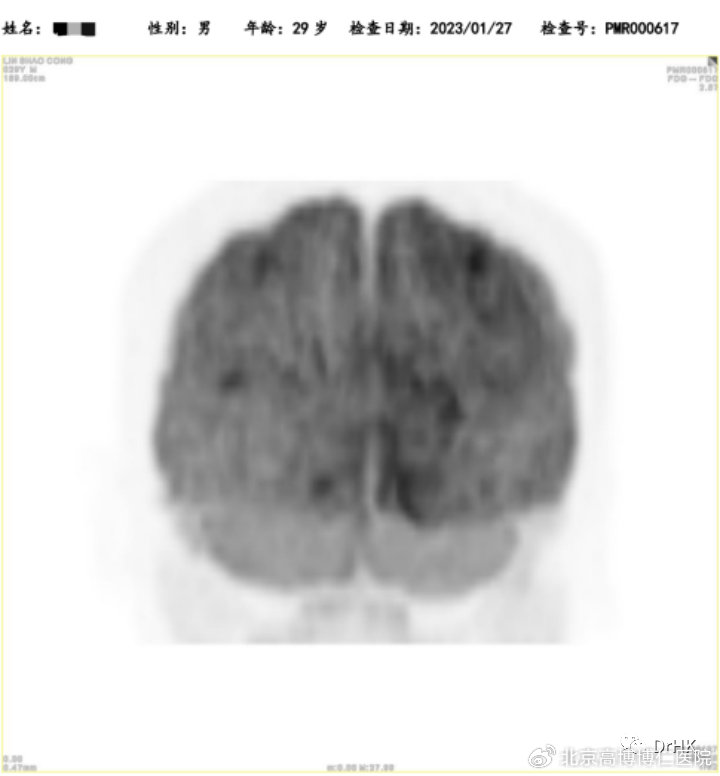

PET-CT:Deauville 评分5分。(1)肝脏累及,大小约3.2*2.6*3.7cm,最大SUV值22.4; (2)脑部:右侧颞叶深部、基底节区稍低密度灶,结合MRI图像,考虑淋巴瘤累及;(3)全身多发骨(双侧肩胛骨、锁骨、肋骨、胸骨、骨盆骨、脊椎骨)多发骨质吸收、破坏改变,部分区域骨质密度增高,以左侧髂骨为著;(4)左侧臀大肌,范围约1.2*1.6*1.5cm,最大SUV 12.4。

随后患者定期随访,分别于移植后半年、一年完善影像学评估,令人欣慰的是患者目前一直保持完全缓解状态。PET如下图所示:

(移植后半年影像学评估)